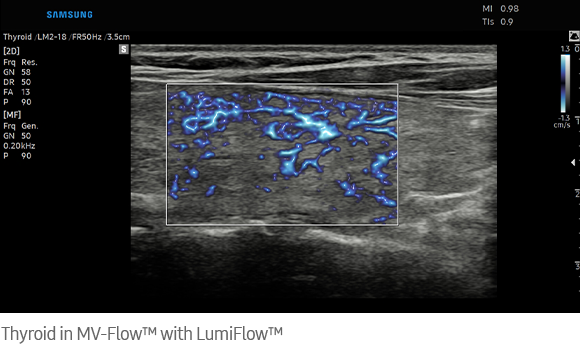

Visualize slow flow microvascularized structures

MV-Flow™ ¹ visualizes microcirculatory and slow blood flow to display the intensity of blood flow in color.

Three dimensional-like visualization of blood flow

LumiFlow™ ¹ is a function that visualizes blood flow in three dimensional-like to help understand the structure of blood flow and small vessels intuitively.